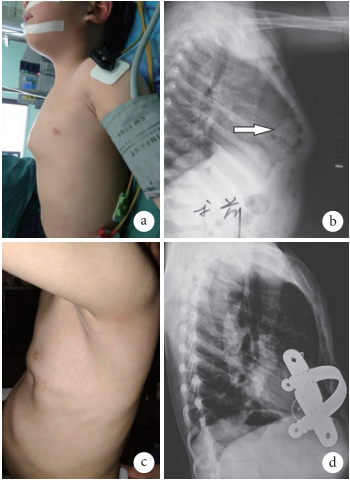

微创一期治疗儿童鸡胸合并胸骨后疝一例

图片尺寸350x481